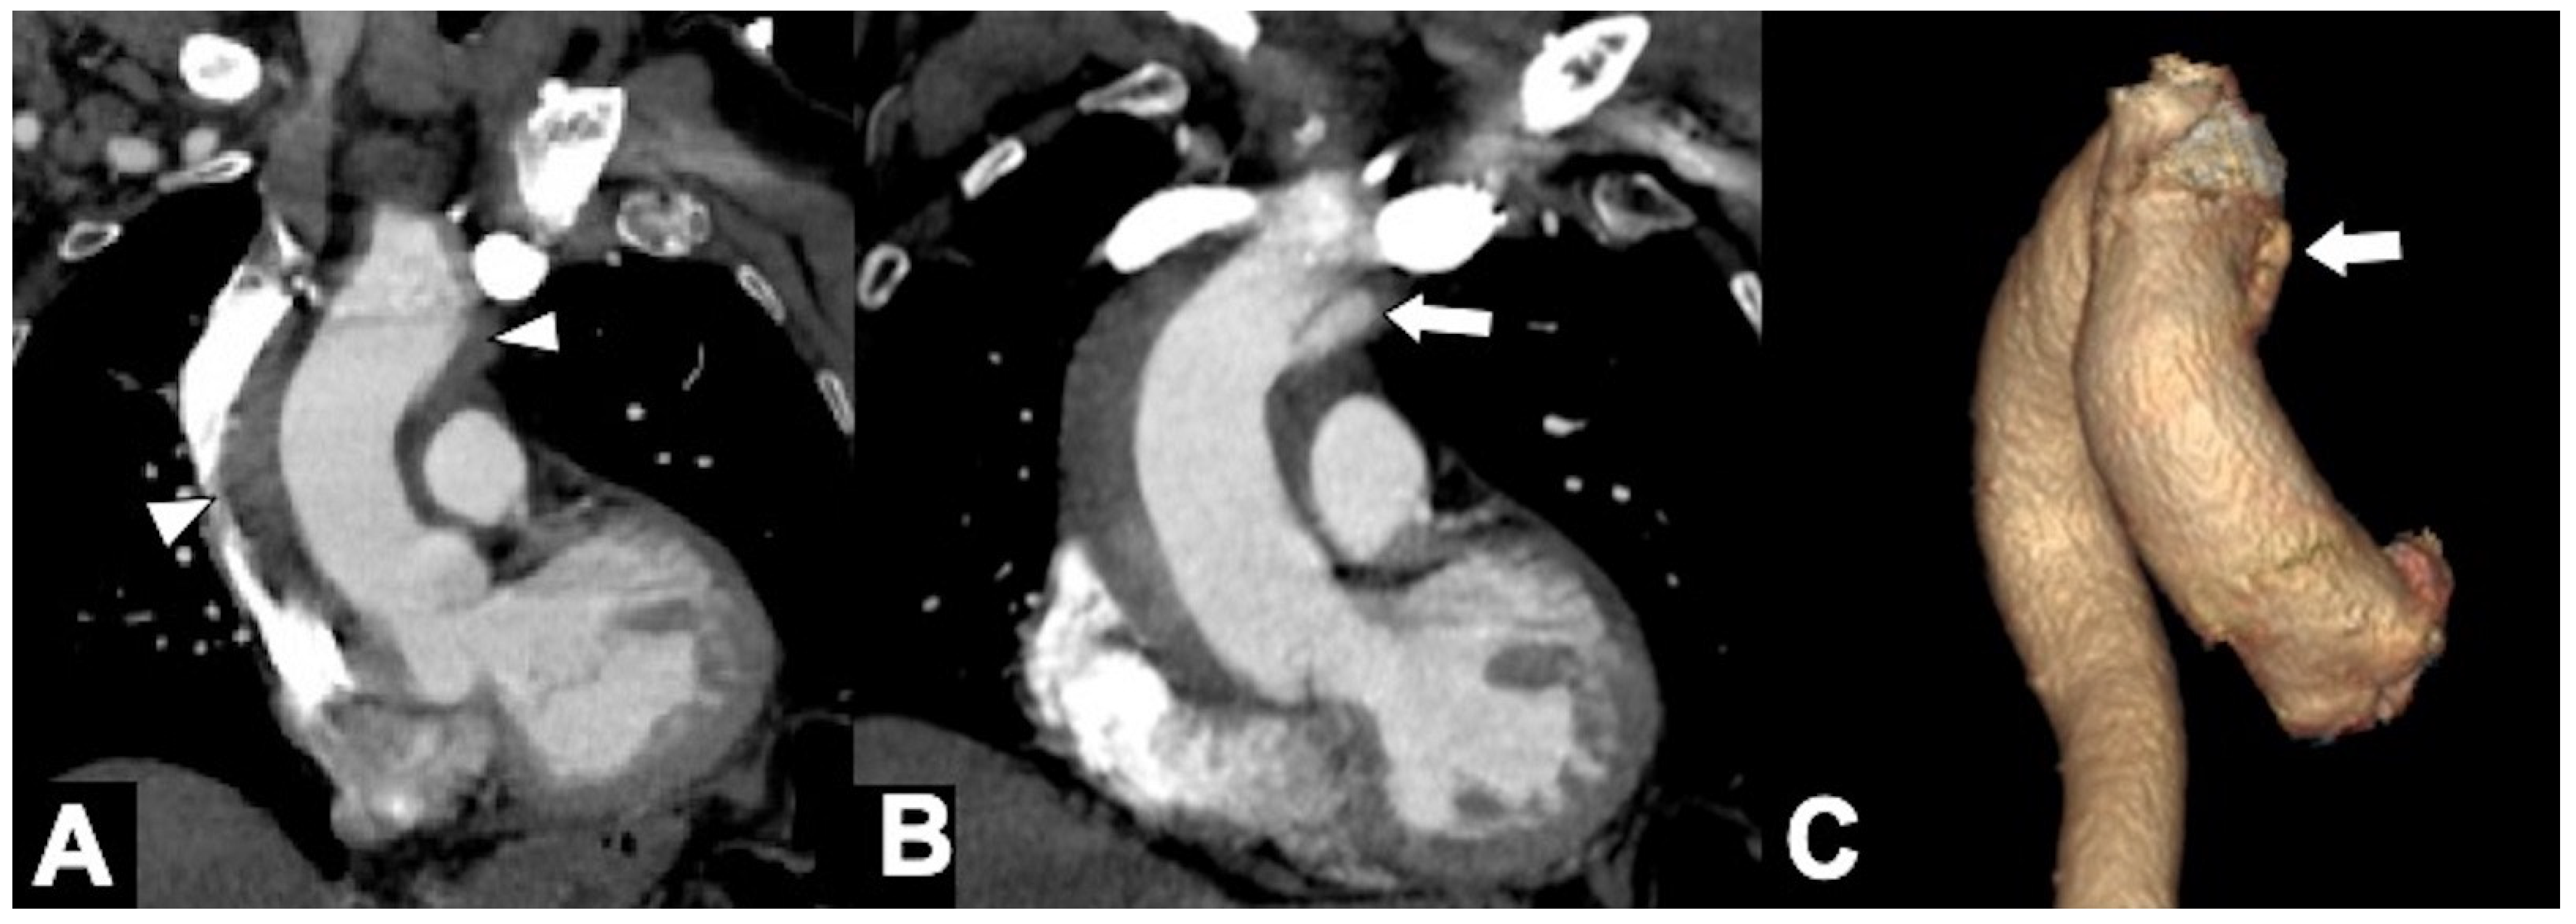

Figure 9. Unstable Type A IMH complicated by ulcer-like projection (ULP). (A) Coronal oblique CTA shows type A IMH (arrowheads) in a 68-year-old man with hypertension and chest pain. The total aortic diameter was less than 50 mm and the IMH thickness less than 11 mm; he underwent medical management initially. (B) Three-day follow-up coronal oblique CTA image shows disease progression by an ULP due to opening of intimal tear (arrow). (C) 3D-volume-rendered (VR) reconstruction confirms ULP (arrow).